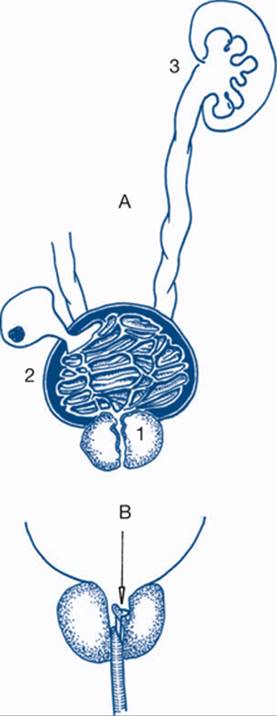

Figure 9.7a Effect of urinary obstruction

A: obstruction effect; 1: prostatic hyperplasia, submucosal venular bleeding; 2: muscle trabeculation, detrusor muscle hypertrophy, bladder diverticula and stone; 3: hydronephrosis and renal failure. B: transurethral resection. The resectoscope is in position. The diathermy cutting loop is drawn back to remove hypertrophied prostate tissue in layers.